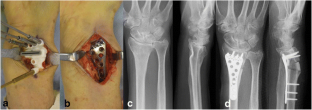

Fig. 2